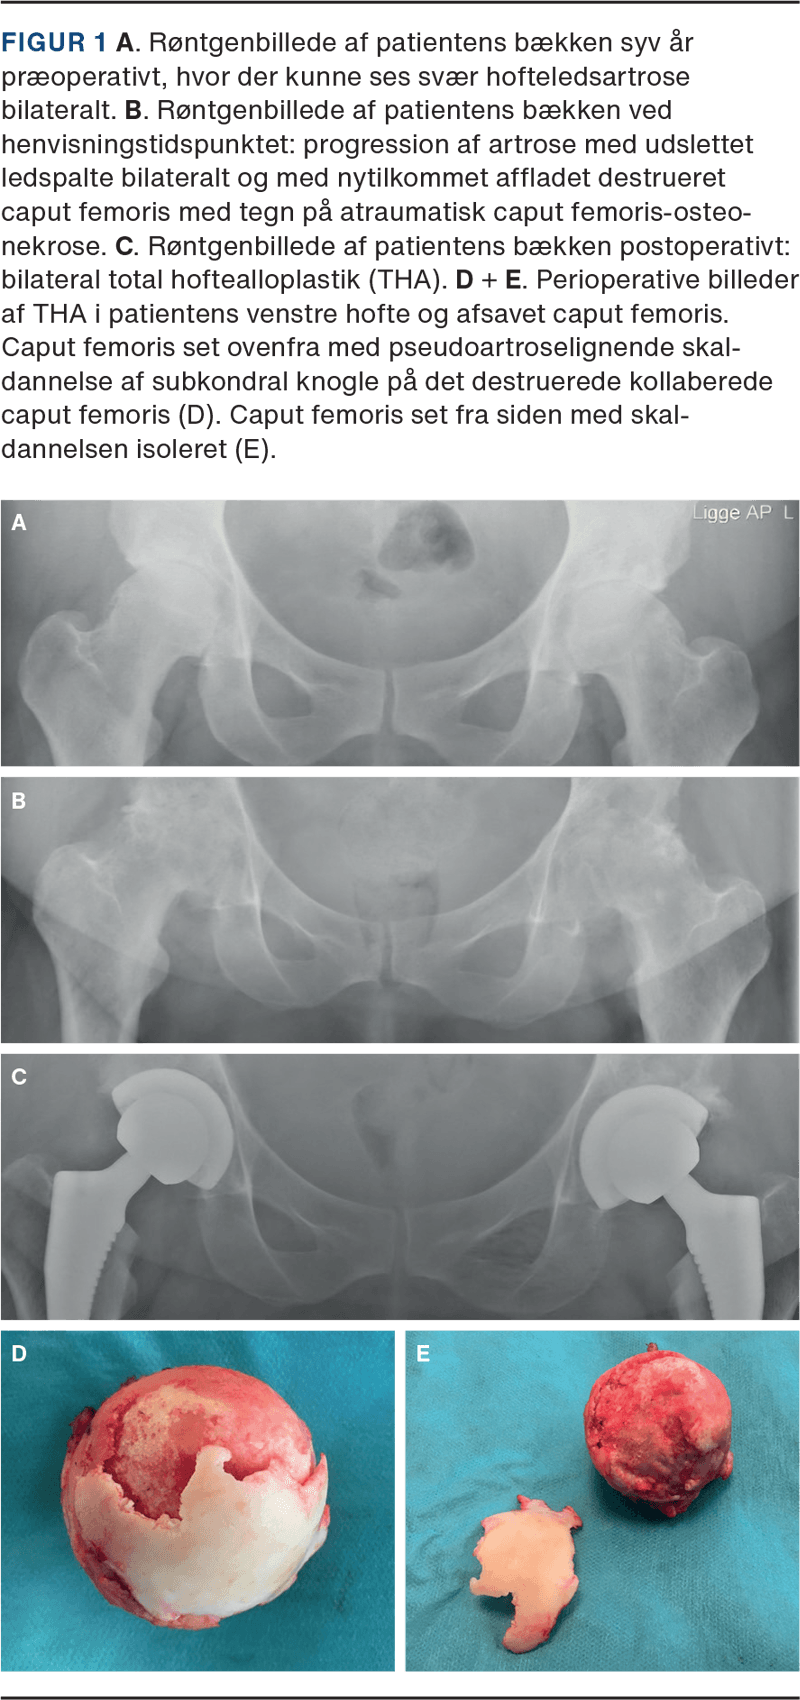

Syv år før den aktuelle henvendelse var hun blevet diagnosticeret med svær bilateral hofteledsartrose med sekundære karakteristika som knoglecyster og CAM-deformitet (Figur 1 A). Hun blev tilbudt THA, men havde på daværende tidspunkt ikke et ønske om operation.

Røntgenundersøgelse viste progression af artrose med udslettet ledspalte bilateralt og nytilkommet affladet destrueret caput femoris med tegn på ON (Figur 1 B). CT viste venstresidigt elementer af PA-dannelse mellem kollaberet caput og subkondral knogle/brusk.

Patienten blev tilbudt bilateral THA med operation ad to omgange. Operationerne blev udført med godt radiologisk resultat (Figur 1 C). Peroperativt blev der fundet PA med skaldannelse af normalt udseende brusk og subkondral knogle med underliggende kollaberet caput femoris, som dermed klinisk understøttede diagnosen ON (Figur 1 D og E).